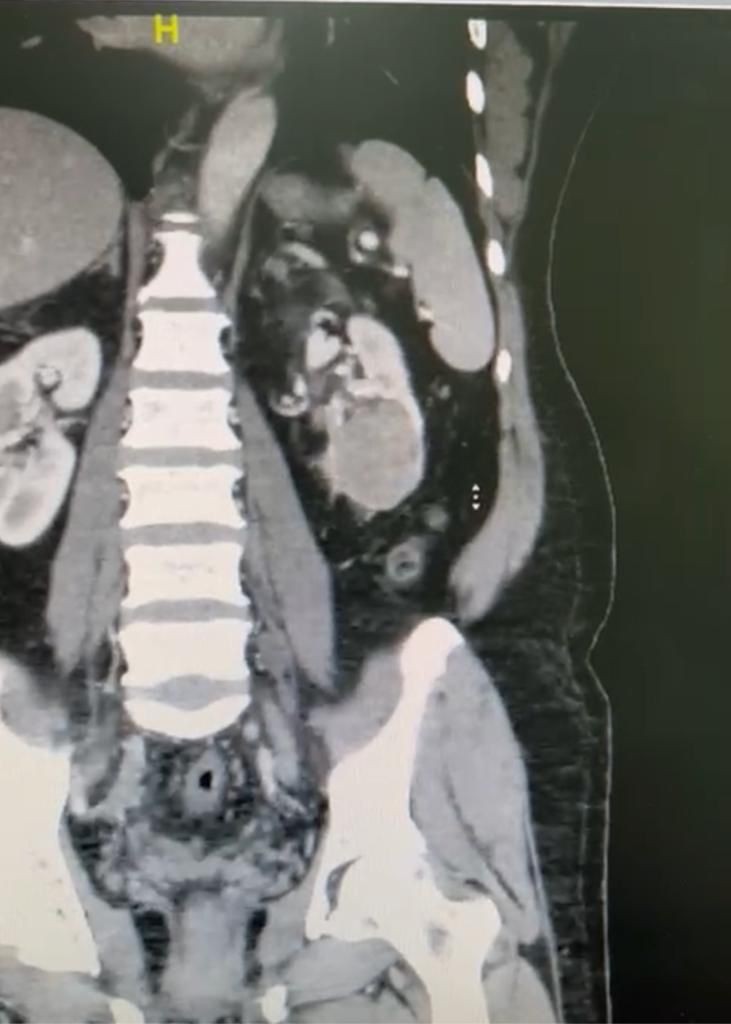

وأفاد بعد استكمال كافة الفحوصات الطبية اللازمة التي بينت نتائجها وجود ورم بحجم 7 سنتميتر في الكِلية اليسرى، حيث اتضح وجود الورم في معظم الكِلية اليسرى للمريض، الأمر الذي استدعى تحضير المريض لنقله إلى قسم العمليات، حيث تقرر التدخل العاجل لإجراء عملية نوعية دقيقة بالمنظار الجراحي.

وقد ساعد في إجراء العملية الدكتور بدر صالح سعداوي إستشاري مسالك بولية وبتعاون ومشاركة الدكتور أحمد فادن إستشاري جراحة عامة ورئيس قسم العمليات وأقسام الجراحة والتي استغرقت 3 ساعات.

جرى فيها استئصال الكِلية اليسرى واستئصال الورم بالكامل، وتكللت بالنجاح بحمد الله، دون حدوث اية مضاعفات للمريض.